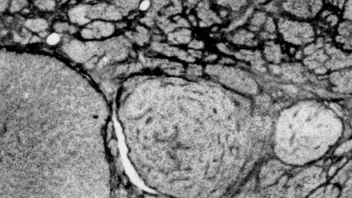

Präparat Zellkultur in 8cm Petrischale, Präparatdicke 35 - 120µm. Färbung alkalische Phosphatase.

Auf den Fotos Bildweite 80µm, Fokusdifferenz li - re 25µm, weisse Pfeile AlP neg Zellen.

Charakterisierung von Nebenschilddrüsengewebe bei reaktivem Hyperparathyreoidismus in Normotrophie - Hypertrophie - Hyperplasie.

Bindegewebe schwarz, Parenchym weiß, Zeichnung vom 0,5µm Schnitt bei 1250fach. Foto Goldner Färbungvon 2µm Schnitt, Aufn bei 470nm, daher Bindegewebe schwarz. -

musste schon alles fokussiert sein, die Kulturzellen sind ja fürchterliche (schiache) Flundern wie Kuhfladen oder schollen, ausserhalb vom Kern 3-5µ dick. das ging nur mit der Wasserimmersion. Für die Fotos hab ich ja bsonders stark gfärbte ausgsucht, meistens wars schwächer.